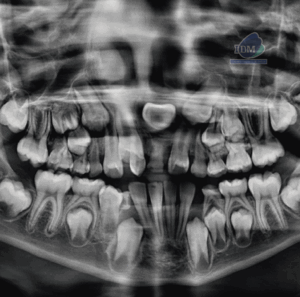

Paciente masculino de 17 años de edad, es referido al Instituto de Diagnóstico Maxilofacial – IDM para evaluación general.En la radiografía panorámica (Figura 1), se